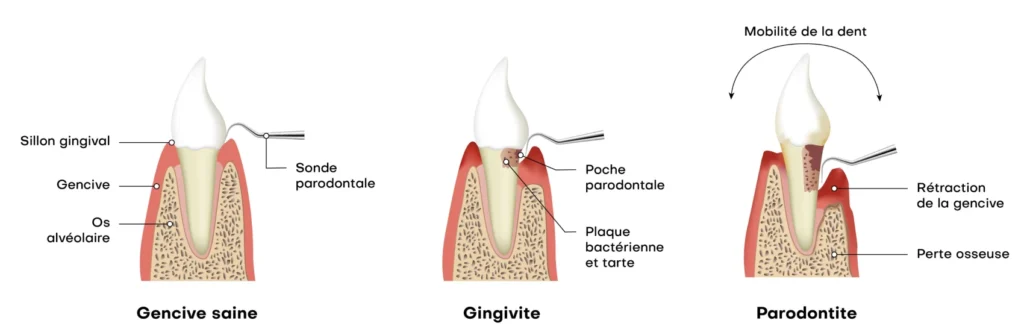

La parodontologie se concentre sur la prévention, le diagnostic et le traitement des infections et des inflammations des tissus de soutien des dents. Elle vise à préserver non seulement la stabilité des dents, mais aussi la santé générale du patient. En effet, les maladies parodontales, comme la gingivite et la parodontite, sont causées principalement par l’accumulation de plaque bactérienne et de tartre autour des dents, mais elles peuvent également être influencées par des facteurs comme le tabagisme, le stress, les déséquilibres hormonaux et certaines maladies systémiques comme le diabète.

Les premiers signes des maladies parodontales peuvent inclure :

- Gencives rouges, enflées ou sensibles

- Saignements fréquents lors du brossage ou de l’utilisation du fil dentaire

- Mauvaise haleine persistante, souvent associée à l’accumulation de bactéries

- Récession gingivale, exposant les racines dentaires et augmentant la sensibilité

- Mobilité des dents ou sensation que les dents se déplacent

- Formation de poches parodontales entre les dents et les gencives, favorisant l’accumulation de bactéries

- Douleurs gingivales ou sensations de pression au niveau des gencives

La parodontite est une forme avancée de maladie des gencives qui touche les structures profondes de la bouche, y compris l’os et les ligaments. Elle peut entraîner des dommages irréversibles si elle n’est pas traitée à temps. Heureusement, un traitement précoce peut stopper l’évolution de la maladie et protéger votre santé bucco-dentaire.

- Gencives rouges et enflées : Un signe d’infection ou d’inflammation. Si vos gencives deviennent rouges et gonflées, cela peut indiquer un début de gingivite, qui peut évoluer en parodontite si non traité.

- Saignements lors du brossage : Les saignements fréquents pendant le brossage des dents sont souvent un symptôme de gingivite. Si cette condition n’est pas traitée, elle peut se transformer en parodontite.

- Mauvaise haleine persistante : L’infection des gencives peut entraîner une mauvaise haleine, qui persiste même après le brossage des dents.

- Dents qui bougent : Les dents peuvent devenir mobiles lorsqu’elles perdent leur soutien. Cela peut être le signe d’une parodontite avancée qui affecte les tissus de soutien des dents.